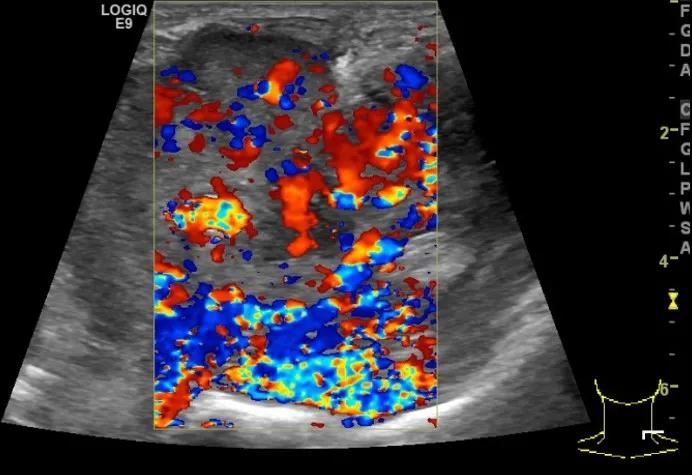

第二例是食管癌患者,术后半年余锁骨上固定淋巴结可触及肿大,疼痛非常明显,系统治疗后无缓解,患者希望通过局部处理缓解症状。造影显示强化信号明显,结节部分区域坏死,故主要针对强化区域从后向前的逐层的消融,皮下进行液体隔离减少烫伤。热消融后影像显示血流增强消失,弹性、硬度增高,一个月后复查显示充盈缺损,完全消融,疗效远超预期。

(病例2图例)